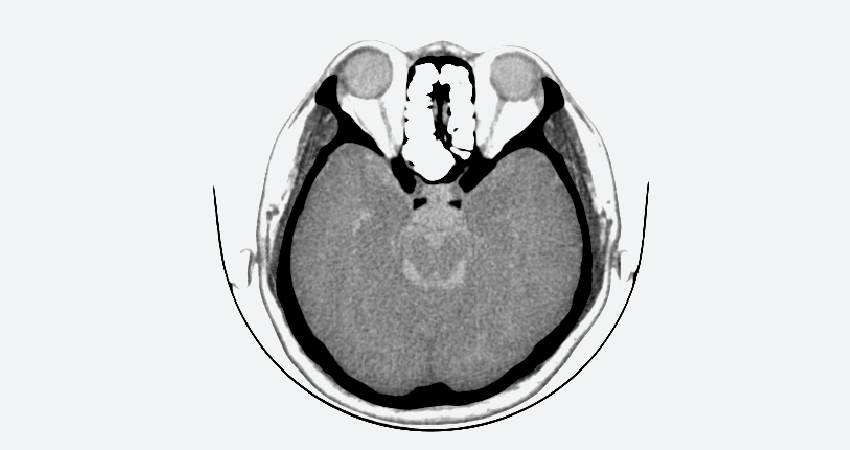

Скриншоты снимков